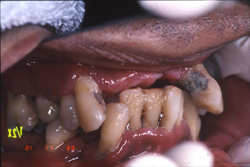

| 歯根周囲の骨が殆んど破壊され全ての歯を抜歯せざるを得ない重度な歯周病。 |

| 上の歯は6本、下の歯は9本残っている。 |

| 歯の動きが大きいため、噛み込むと正常な位置よりかなり沈みこんでしまう。そのため食事が大変、不便である。 |

下の歯の裏側に多くの歯石がついている。この歯石が骨を溶かす原因となる。 |